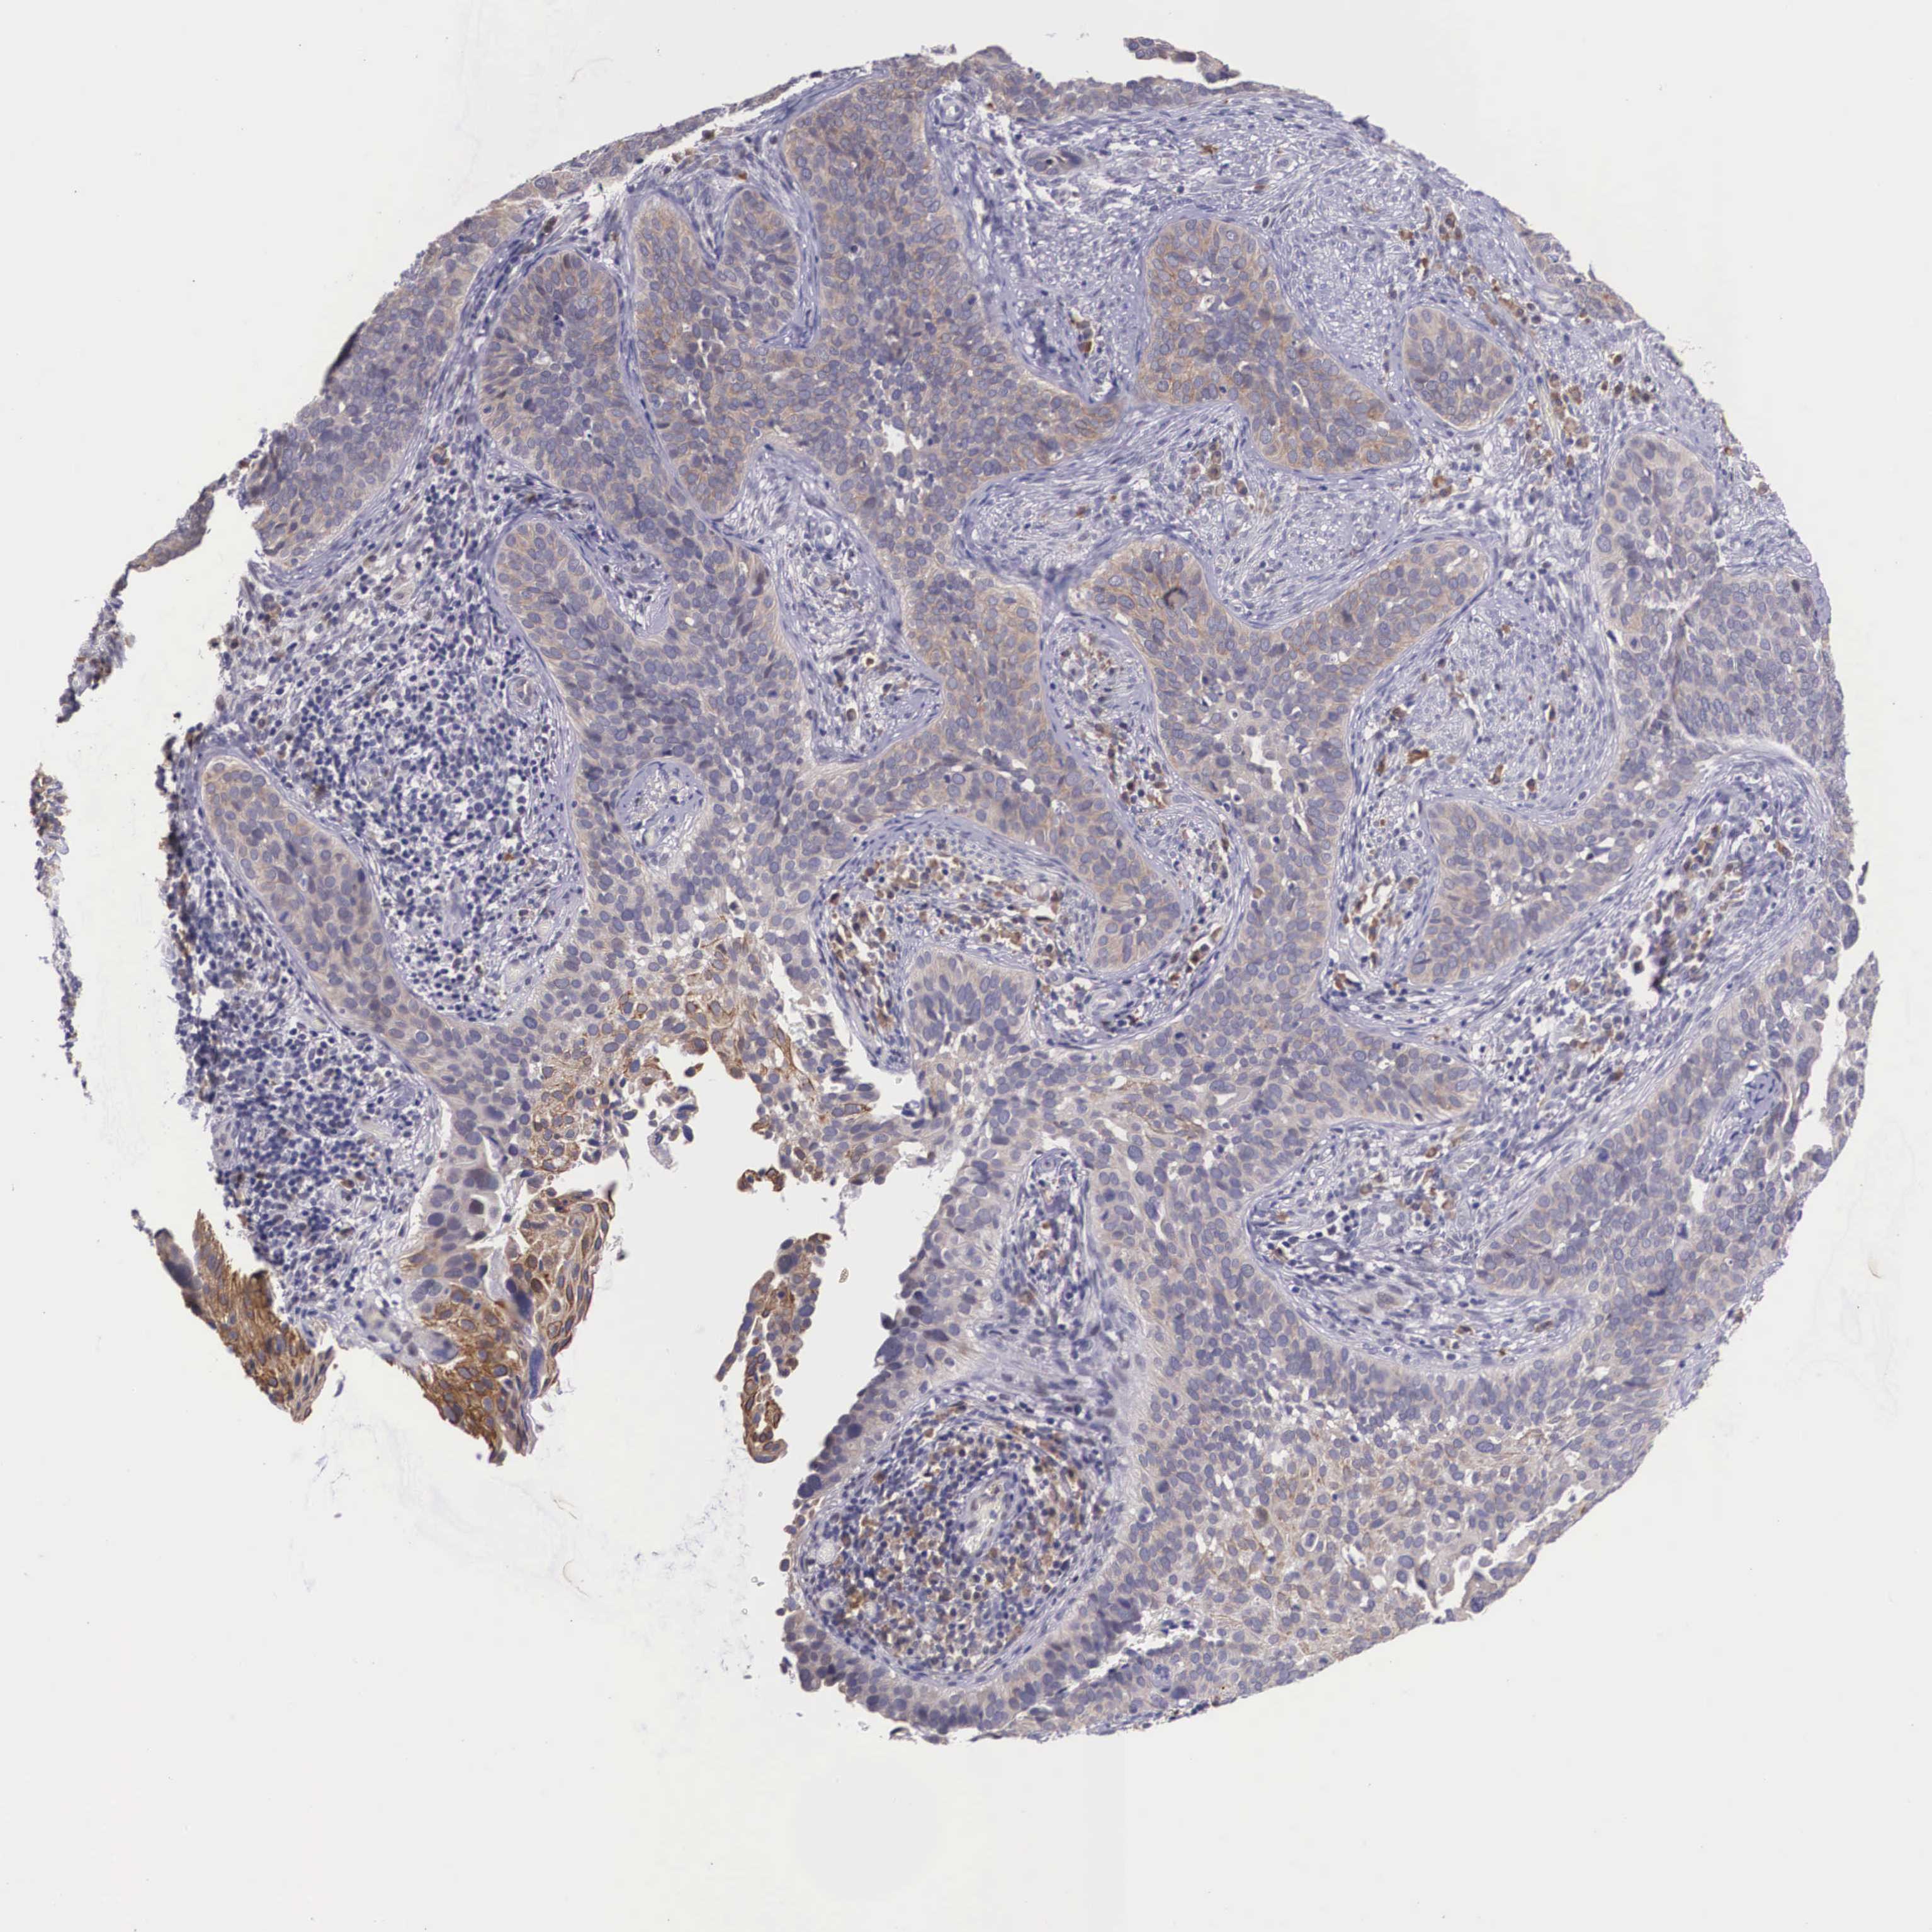

CERVICAL CANCER - Protein expressioni

A mouse-over function shows sample information and annotation data. Click on an image to view it in a full screen mode. Samples can be filtered based on level of antibody staining by selecting one or several of the following categories: high, medium, low and not detected. The assay and annotation is described here.

Note that samples used for immunohistochemistry by the Human Protein Atlas do not correspond to samples in the TCGA dataset.

Antibody stainingi

Antibody staining in the annotated cell types in the current human tissue is reported as not detected, low, medium, or high, based on conventional immunohistochemistry profiling in selected tissues. This score is based on the combination of the staining intensity and fraction of stained cells.

Each image is clickable and will lead to virtual microscopy that enables deeper exploration of all samples and also displays staining intensity scores, fraction scores and subcellular localization as well as patient and tissue information for each sample.

Antibody HPA000662

Staining

High

Medium

Low

Not detected

Intensity

Strong

Moderate

Weak

Negative

Quantity

>75%

75%-25%

<25%

None

Location

Nuclear

Cytoplasmic/membranous

Cytoplasmic/membranous,nuclear

Squamous cell carcinoma, NOS